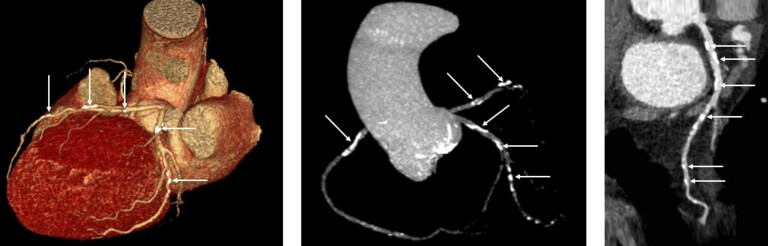

Kireçlenmeyi görmek için görüntüleme cihazları kullanılır. Kireçli damar tanısını koyarken en sık karşılaştığımız senaryolar şunlardır:

- Kalp check-up’ı için çekilen bilgisayarlı tomografide kireç saptanması (kalsiyum skoru)

Sadece kalsiyum skoru için yapılan bilgisayarlı tomografide damarlarda tıkanıklık olup olmadığı anlaşılamaz. O nedenle, risk faktörü olanlarda check-up yapılırken sadece kalsiyum skorunu ölçmek yerine damarların anatomisini ve dolayısıyla tıkanıklık olup olmadığını gösteren BT anjiyoyu (sanal anjiyo) yapmak genellikle daha doğrudur. BT anjiyoda, kalsiyum skoru (Agatston skoru) zaten ölçülür. Ancak, BT anjiyo çekiminde; sadece kalsiyum skoru için yapılan BT çekimine kıyasla hastaya verilen radyasyon miktarı daha fazladır ve damarların görülebilmesini sağlayan kontrast madde denilen boyanın kullanılması gerekir. Sonuçta, hangi tür BT çekiminin daha uygun olacağının kararı hastadan hastaya değişir.